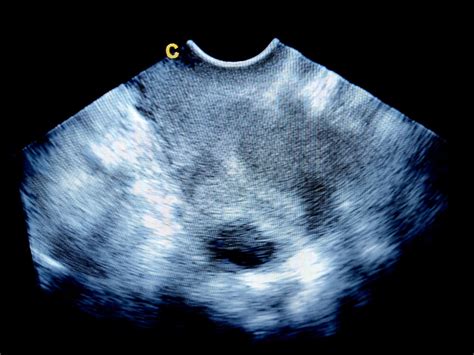

Diagnostika miomov

Zanesljivo diagnosticiranje teh nepravilnosti je ključnega pomena za uspešno zdravljenje. Hiter razvoj ultrazvočnih aparatov nam je omogočil zelo zanesljivo ugotavljanje teh napak. Ultrazvočni pregled je zato ena prvih preiskav, ki jo opravimo ob težavah z zanositvijo. V nekaterih primerih, zlasti ko je potrebna natančnejša vizualizacija ali kadar ultrazvok ni dovolj zanesljiv, se lahko uporabi tudi magnetna resonanca (MR) ali histeroskopija. Histeroskopija omogoča neposreden vpogled v maternično votlino in odstranitev patoloških sprememb.